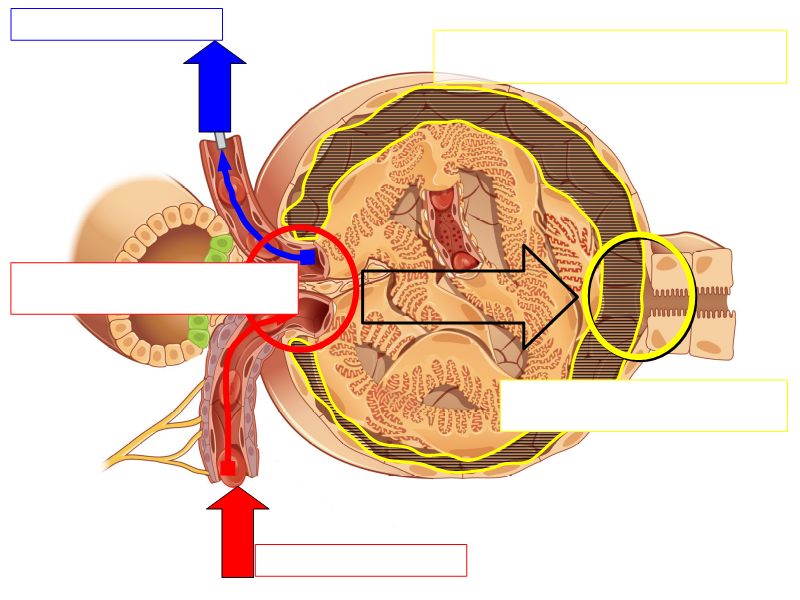

Kidney

- Capsule

- Cortex

- Medulla

- Multilobar

Multilobar

- Conical mass (pyramid)

- Medullary tissue

- capped with

- Cortex

- Delineated by

- Renal columns

- Apex of pyramid

- Papilla

- Projects into renal pelvis

Pyramid

- Simple columnar epithelium

- Continuous with transitional epithelium

Capsule

- Irregular dense CT

- Surrounded adipose tissue

Blood flow

- Efferent arteriole

- Smooth muscle in media

- Capillaries

- Fenestrated

- Afferent arteriole

- Smooth muscle in media